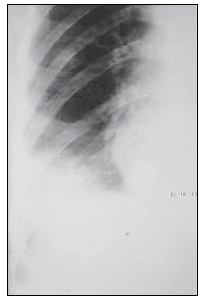

“Paciente apresenta o seguinte exame de radiografia torácica.”

Assinale a alternativa que apresenta corretamente o sinal presente no exame.